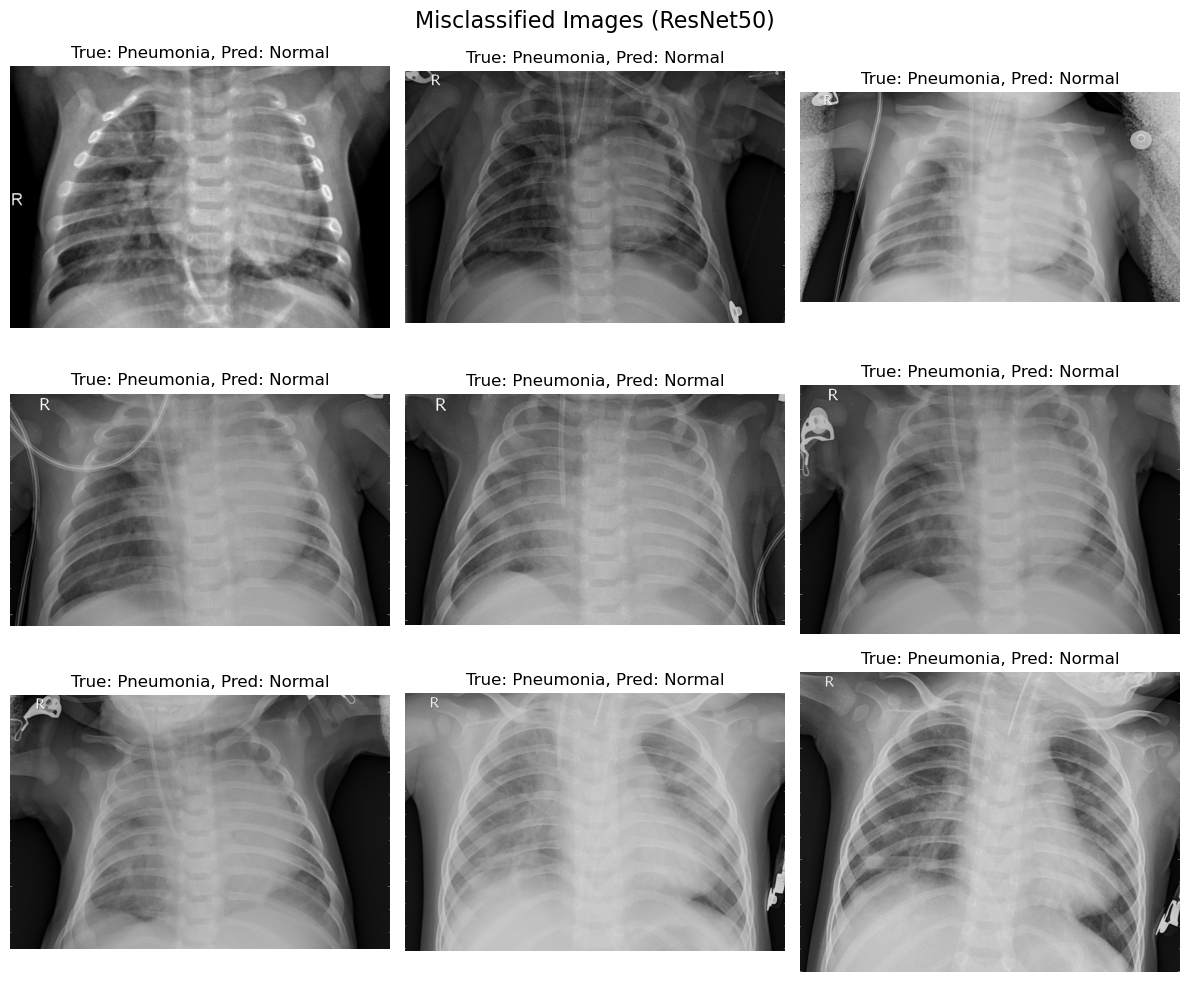

The comparison of the misclassified images from the two models, EfficientNetB0 and ResNet50, provides valuable insights into the strengths and weaknesses of both approaches in diagnosing pneumonia from chest X-ray images.

ResNet50:

i. Normal Class: Achieved better accuracy for normal cases compared to EfficientNetB0, with fewer false negatives.

ii. Pneumonia Class: Maintained a balanced trade-off between precision and recall, suggesting more reliable generalization.

Model Selection:

i. While both models perform well, ResNet50 is the recommended choice for practical applications due to its ability to minimize misclassifications and provide consistent performance.

i. Misclassifications must be studied in greater detail, as false negatives (pneumonia classified as normal) have significant consequences in clinical decision-making.

ii. A system incorporating ResNet50 with additional interpretability techniques (e.g., Grad-CAM or LIME) could support radiologists in identifying critical cases.

The comparative analysis highlights ResNet50 as the superior model for diagnosing pneumonia, with its deeper architecture enabling better feature extraction and classification performance. However, EfficientNetB0 remains a valuable alternative in scenarios where computational efficiency is a priority. Future work should explore advanced fine-tuning and ensemble methods to further enhance diagnostic accuracy.

This matrix shows results identical to those of EfficientNetB0: